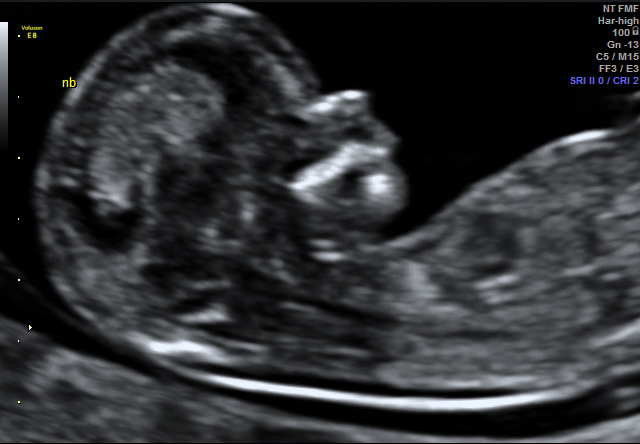

I don't have a complete shot head to toe of baby with nub exposed but I do have a close up... All guesses appreciated!